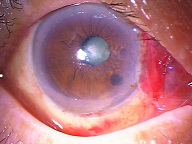

今日いらした24歳女性の症例です。

強い充血を認めます。写真の右側は、はやり目に特徴的な後遺症で、黒目(角膜)が濁っている写真です。もう少し分かりやすい、ヒドイ症例の写真を出したいのですが、ヒドイ症例は第一診察室には入らないようにしていただいたり、写真をとるなどの、余分な時間を少しでも省いて診療を行い、院内感染を予防する必要があり、なかなか難しいのです。